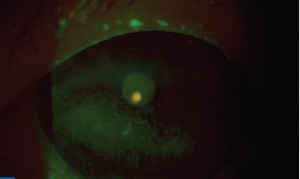

A 68-year-old White woman was referred for persistent keratitis OS and failure on multiple medications. Find out her official diagnosis and treatment plan.